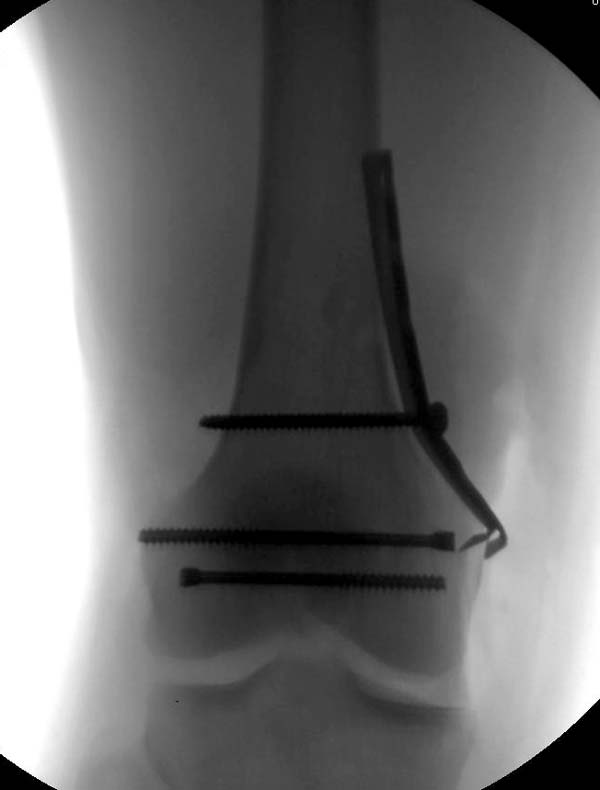

[Ortho] Нелеченный перелом Hoffa

Здесь представлены различные варианты фиксации перелома, а также снимки

комбинации перелома с повреждением хряща (12-19). Пластика хряща

OsseoFit и установка custom made plate.